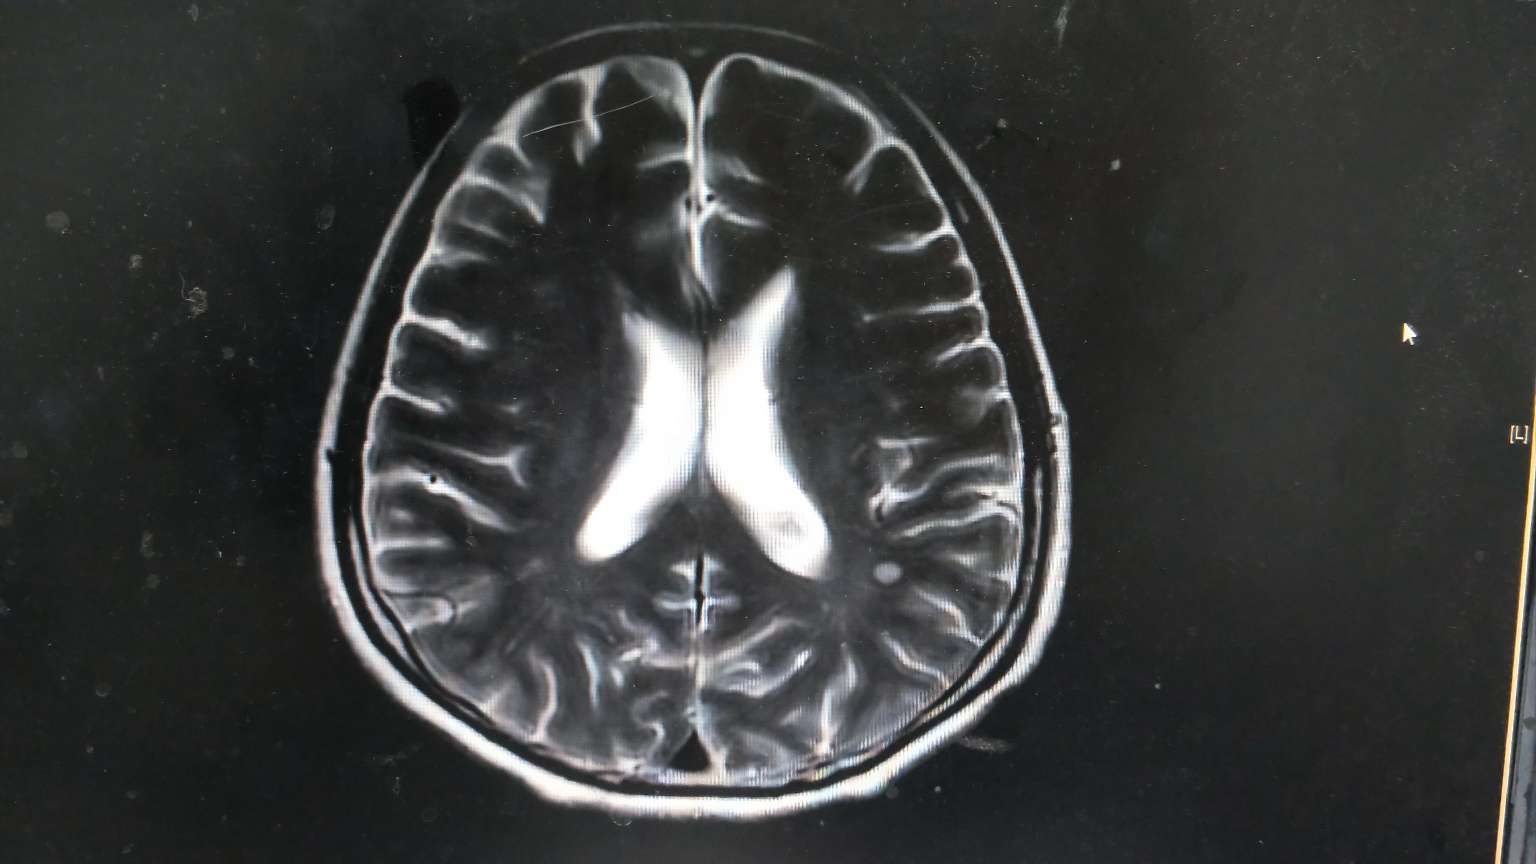

★颅脑左额叶和顶叶结节,双侧基底节区及半卵圆中心多发腔隙灶。